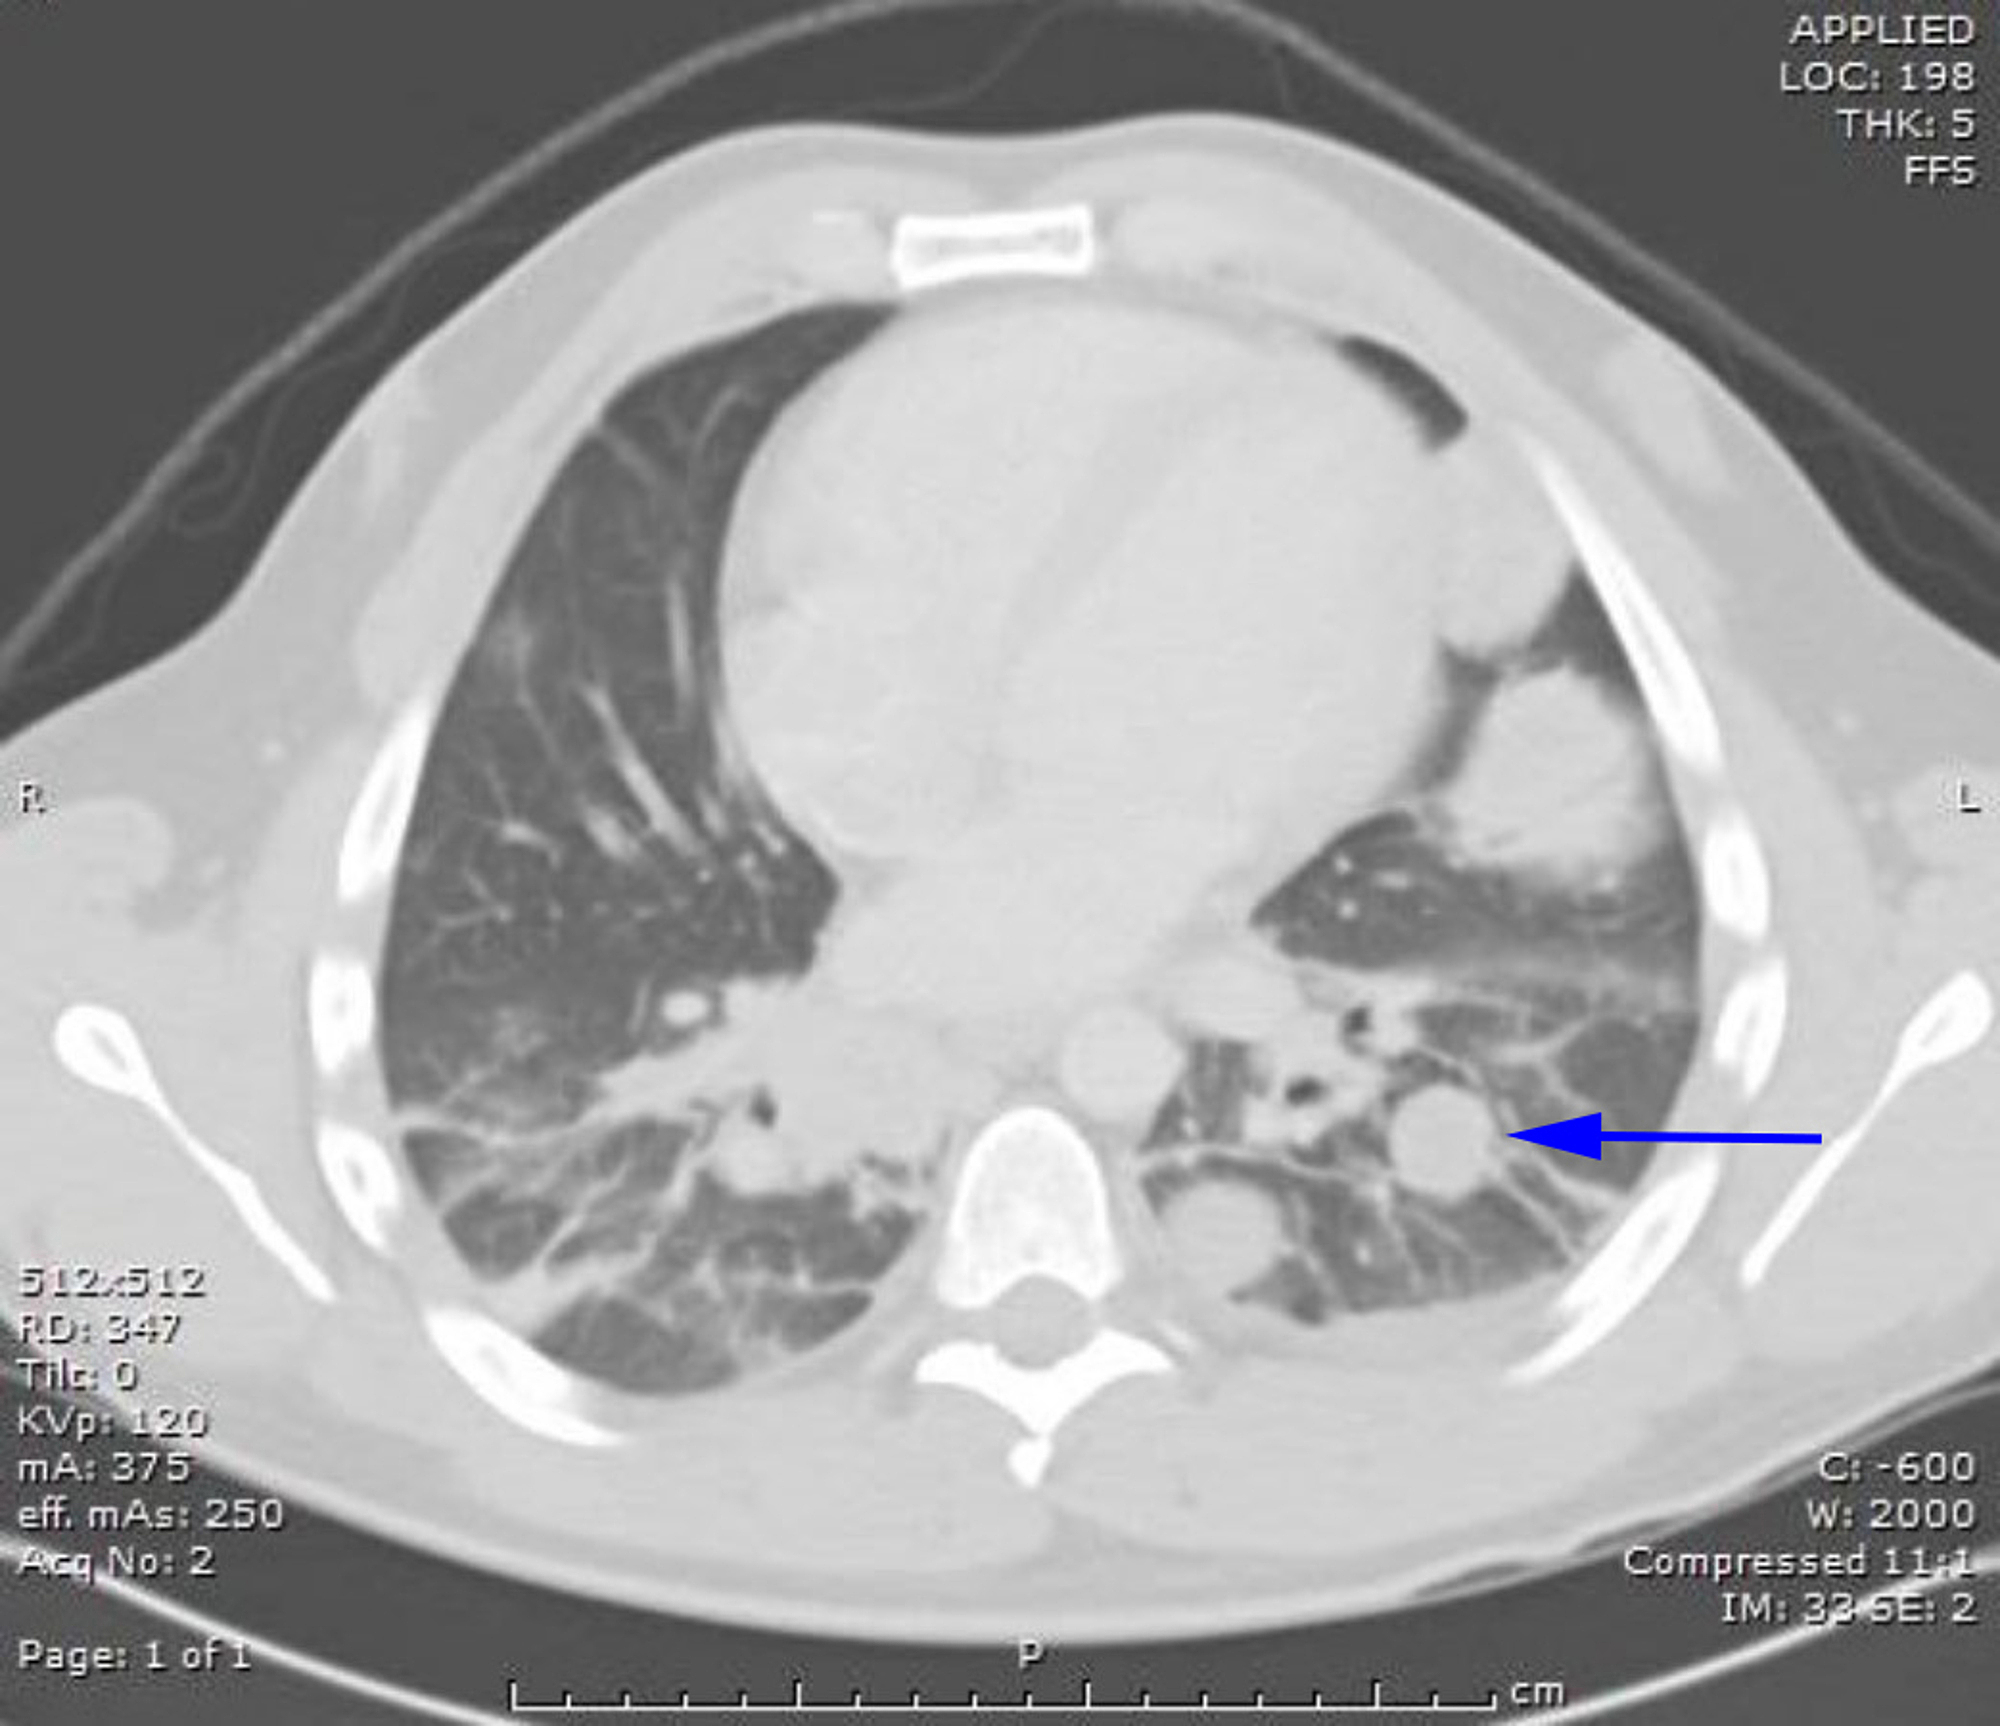

Brain CT of a young man with testicular germ cell tumor is showing Testicular Cancer Brain Metastases Common treatments for brain metastases from testicular primary cancers include surgical resection, whole brain radiation (wbrt), stereotactic radiosurgery (srs), or combinations of these methods. Testicular cancer with neurological symptoms indicates brain metastases. We found that brain tumors from testicular cancer are very rare, found in just 0.4% of the patients we studied. Testicular cancer with neurological symptoms indicates brain metastases.. Testicular Cancer Brain Metastases.